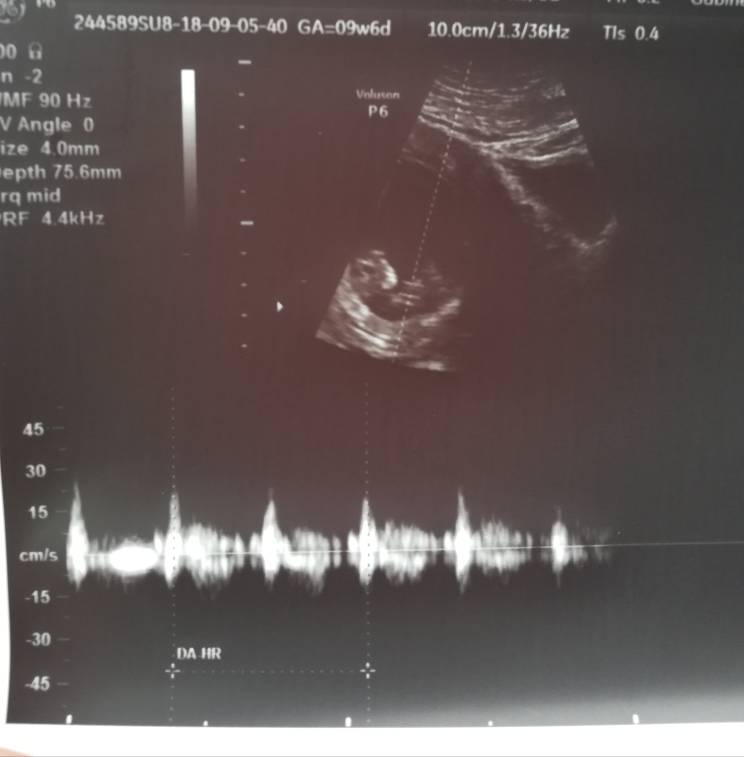

) Dzidziuś ma ponad 1,5 cm. Serduszko bije, słyszałam i mam nagrane